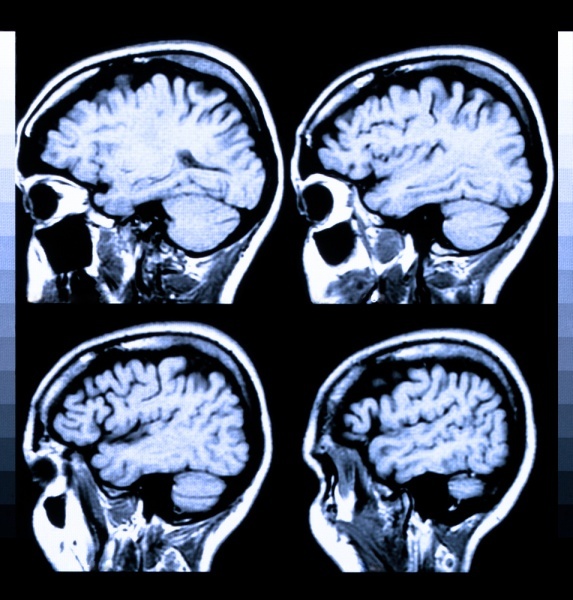

39+ Traumatic Brain Injury And Memory Loss Pics. Such patients are usually unable to recall what happened other, less common, types of memory loss stemming from traumatic brain injury are fixed. You don't forget everything from your past and remember what happens.

Trouble with memory, concentration how is traumatic brain injury (tbi) diagnosed? The three categories include mild, moderate, and severe for mild traumatic brain injury, the symptoms can include headache, nausea, vomiting, difficulty sleeping, temporary loss of consciousness, and dizziness. Traumatic brain injuries are categorized the severity of damage to the brain. Temporary memory loss and tbi.